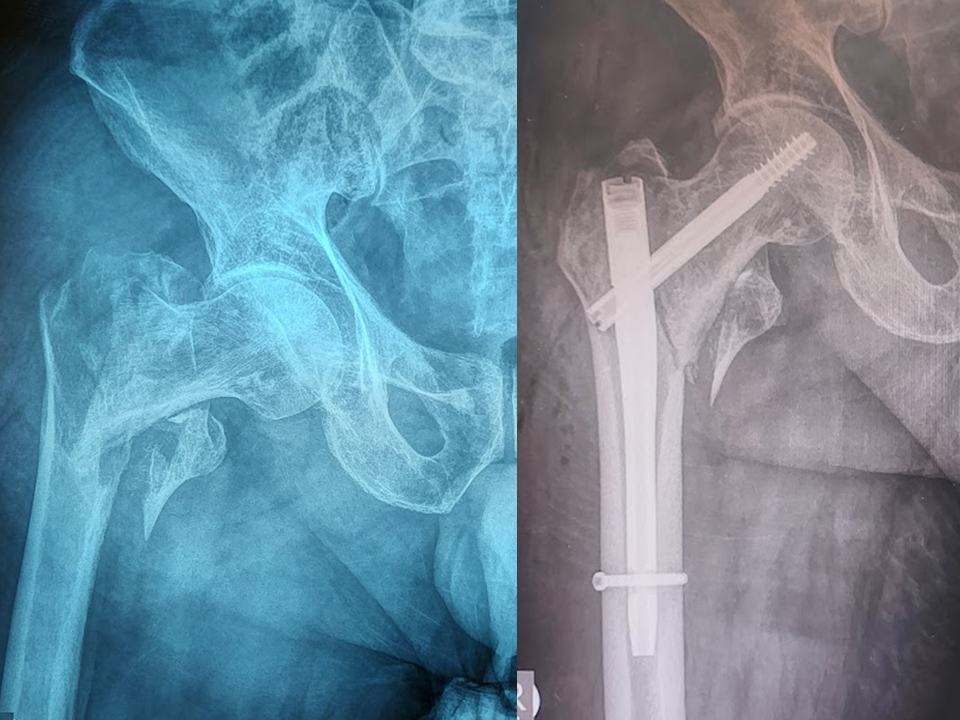

Η ύπαρξη του κεντρικού οστεοφύτου

της κοτύλης φαίνεται ότι δημιουργεί ένα δυσμενές μετεγχειρητικό αποτέλεσμα σε

ασθενείς που υποβάλλονται σε αρθροσκόπηση ισχίου για μηροκοτυλιαία πρόσκρουση.

Η αφαίρεσή του ή όχι αποτελεί ένα

αμφιλεγόμενο θέμα, καθώς το κεντρικό οστεόφυτο προκαλεί πλάγια μετατόπιση (lateralization) της μηριαίας κεφαλής με αποτέλεσμα την απώλεια της

επαλληλίας των δύο αρθρικών επιφανειών και τη γρηγορότερη φθορά του αρθρικού

χόνδρου.

Σε μία νέα μελέτη έγινε η

σύγκριση ασθενών με ύπαρξη κεντρικού οστεοφύτου με μία ομάδα χωρίς την ύπαρξή

του.